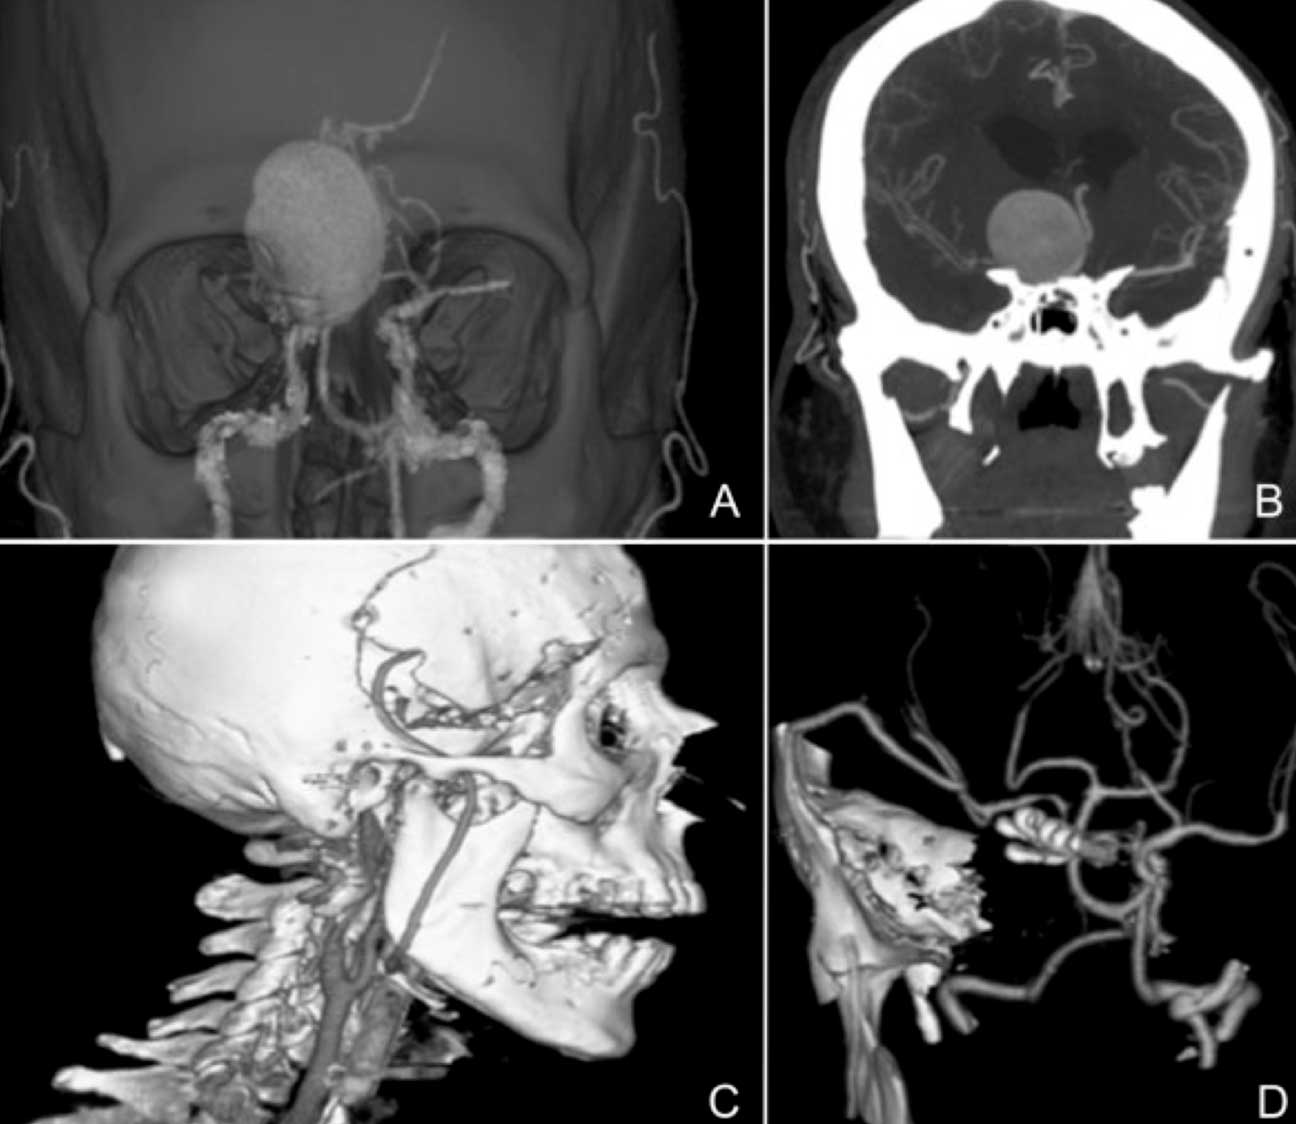

Uso da Artéria Tireoidea Superior como um vaso doador em revascularização extra e intracranial

As anastomoses microvasculares em By-pass podem ser necessárias no tratamento de aneurismas gigantes e tumores da base do crânio. Este artigo relata a Técnica criada pelo Prof. da Universidade do Chile, Dr. Jorge Mura , e descrita pelo Dr. Isolan neste artigo que foi publicado na revista Skull Base de Nova York.

Uso da Arteria Tireoidea Superior como um vaso doador em revascularizacao extra e intracranial